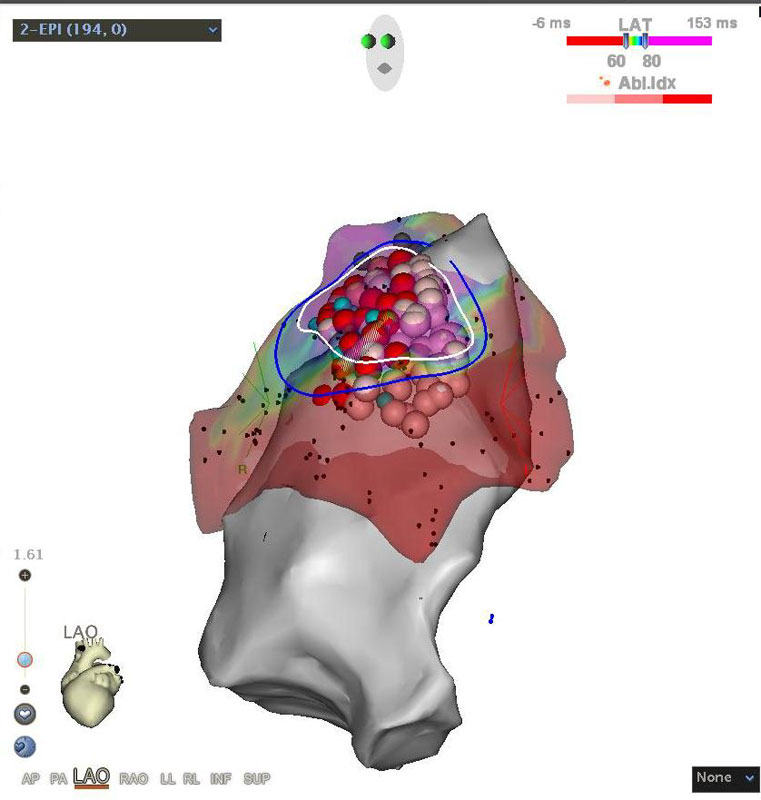

С 2021 г. в Лаборатории диагностики и лечения эпилепсии Отделения нейрохирургии стационара стали проводить радиочастотную термодеструкцию выявленных эпилептогенных очагов одновременно с проведением инвазивного стерео ЭЭГ мониторирования.

Впервые в России выполнена эпикардиальная абляция при синдроме Бругада

В Пироговском Центре создана соответствующая мировым требованиям эпилептологическая служба:

- Мультидисциплинарная команда (врачи разных специальностей, инженеры, лингвисты, математики и аналитики, специалисты IT)

- Высокотехнологичная нейрохирургическая служба

- Современная нейрофизиологическая лаборатория

- Передовая анестезиологическая служба

- Современная нейровизуализация (МРТ, ОФЭКТ, SISCOM)

Внедрен современный протокол диагностики эпилептогенных очагов головного мозга — протокол SISCOM (Subtraction Ictal SPECT Co-Registered to MRI)

Внедрение хирургического лечения эпилепсии с роботизированным инвазивным нейромониторингом